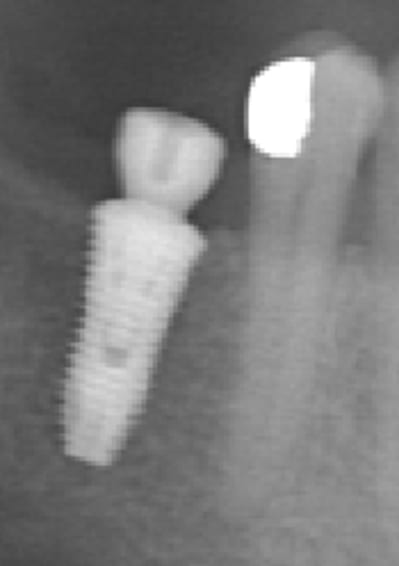

pose d'un axiom en 4*12 en juillet en sous crestal comme il le faut.

et aujourd'hui raido début de cratérisation : petite mais existante;

pour la forme et le fond pano avant retro à la pose et rétro aujourd'hui

fouilla, n'enfoui pas le krestal, ce n'est pas une conception de cone morse, donc laisse la tete de l'implant dépasser un chouilla, sinon tu va cratériser systématiquement; j'ai eu la même type de probleme au début mais j'ai rectifié le tire et ça va impec maintenant.

pour info déja trois cas similaires au maxillaire pas à la mandibule.

et c'est un axiom en 4*12 pas un krestal